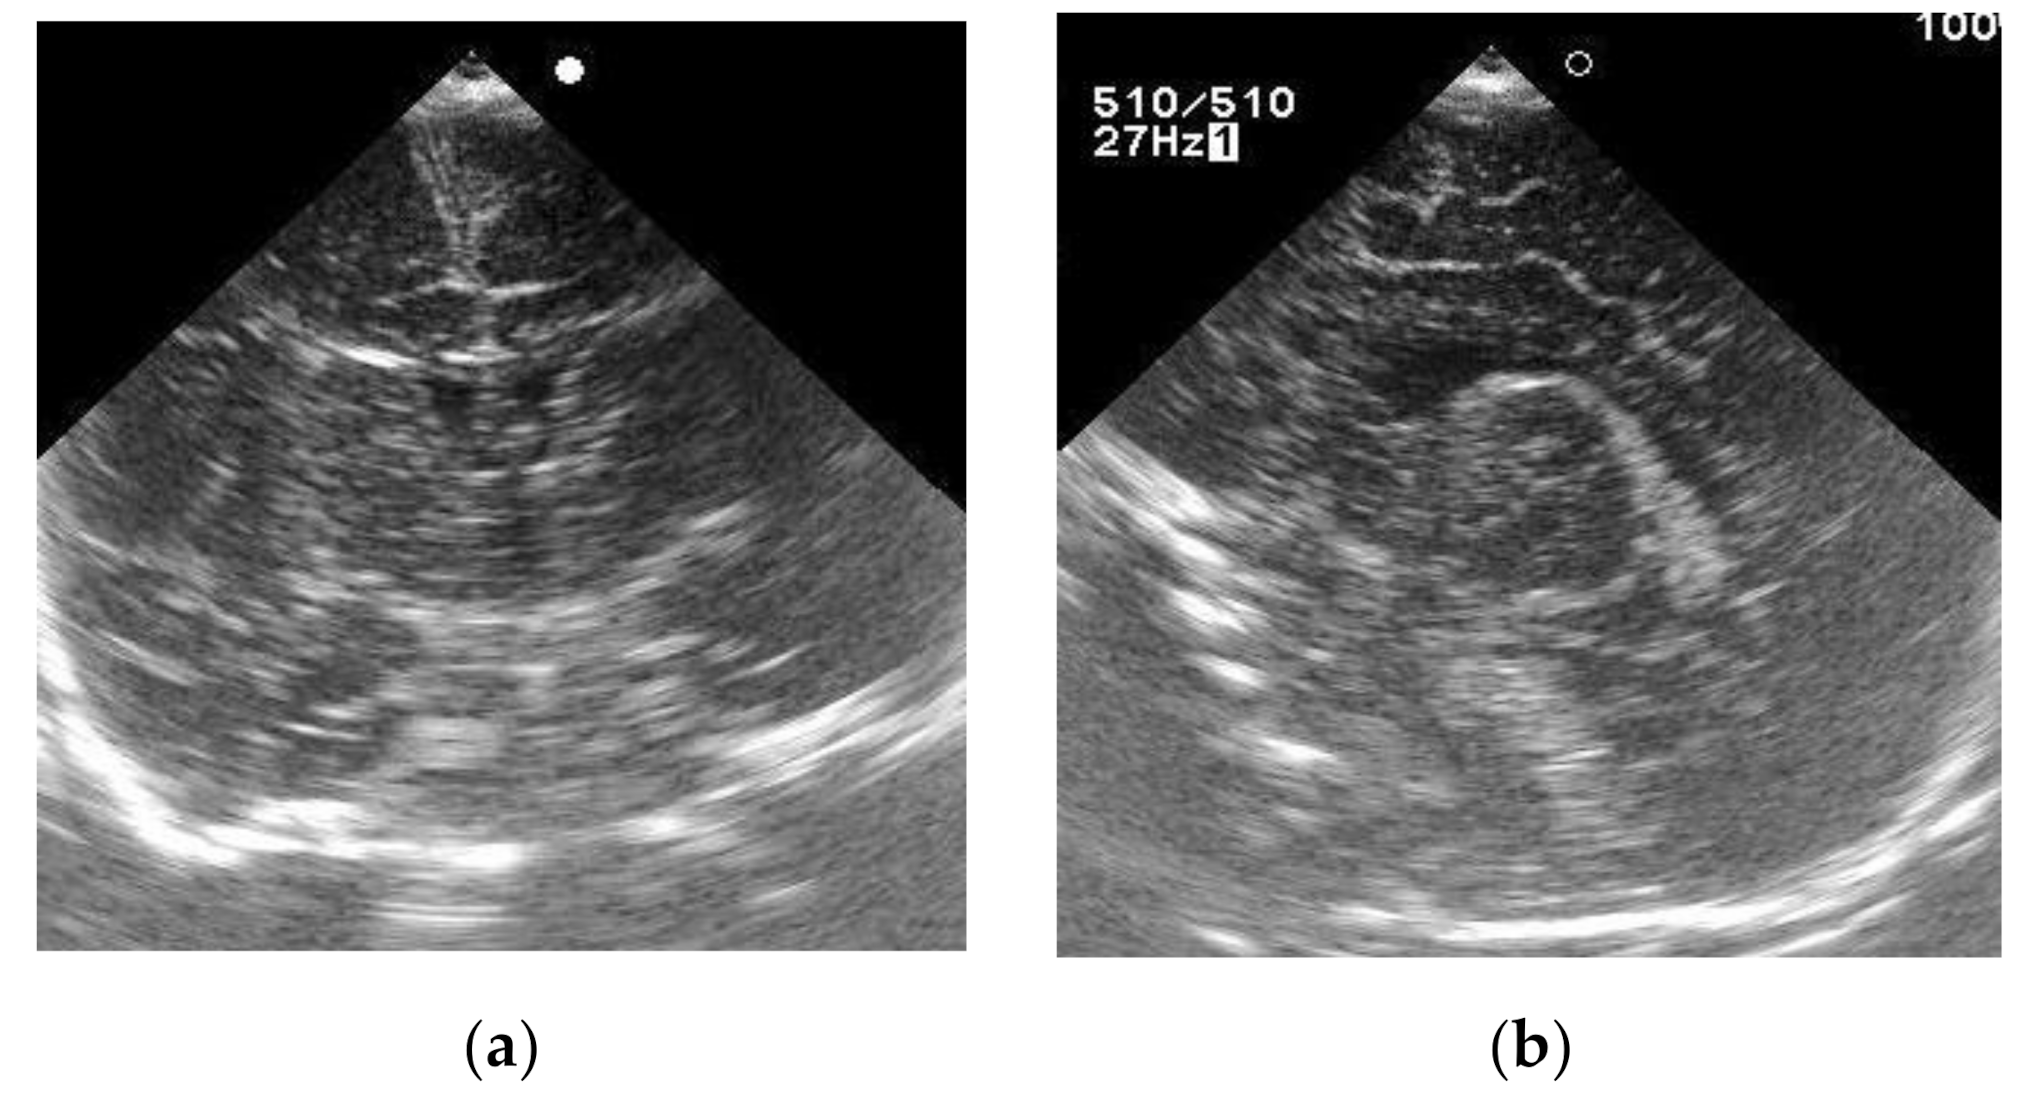

A baby girl born as the first child of healthy nonconsanguineous parents at 40 weeks’ gestation weighed 2810 g at birth, and NS results were normal. However, her sucking was weak and her weight gain was poor. From 2.5 months of age, she presented with hypertonia and the setting-sun eye phenomenon. Although ultrasonography of her brain at 13 days old showed no abnormal findings (Figure 1), head magnetic resonance imaging (MRI) at 2.5 months revealed marked ventricular enlargement, suggesting hydrocephalus or brain atrophy (Figure 2). She underwent ventricular drainage, but respiratory failure became evident at 4 months of age when there was no improvement in head MRI findings. Further diagnostic analysis revealed plasma tHcy levels of 170 μmol/L (normal range, 3.7–13.5 μmol/L) and urinary Hcy levels of 510 μmol/mg·cre (reference value, “undetectable”), suggestive of homocystinuria. As plasma Met level was as low as 3.4 μmol/L (normal range, 18.9–40.5 μmol/L), defects in homocysteine remethylation were indicated. A Met decrease in the NS DBS was also ascertained retrospectively (6.6 μmol/L).

Figure 1.

Brain ultrasonography of Case 2 at 13 days of age. (a) Coronal plane; (b) sagittal plane.